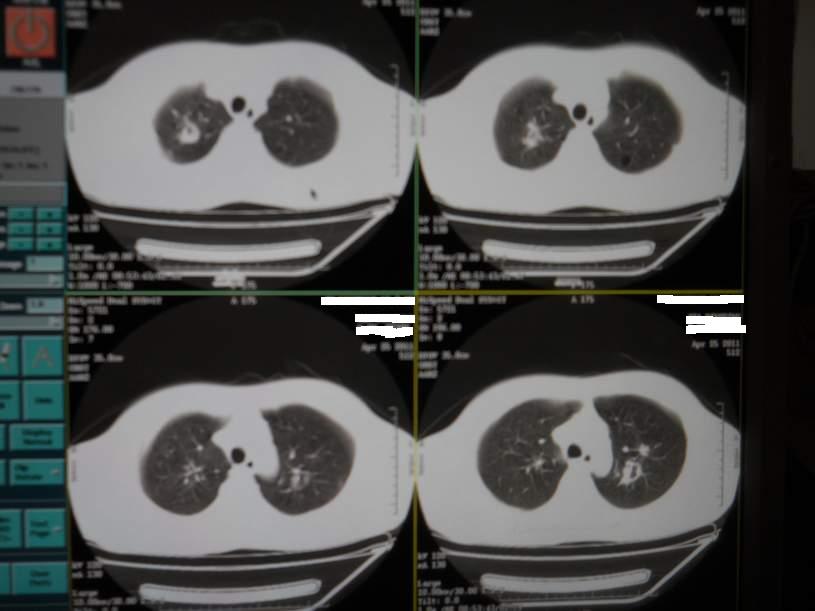

肺霉菌感染

男,22岁,一年前诊断马尔菲尼青霉菌感染,多次复查CT。多次HIV阴性。最近两次CT图片。有实验室结果。

最近实验室检查结果:霉菌感染。